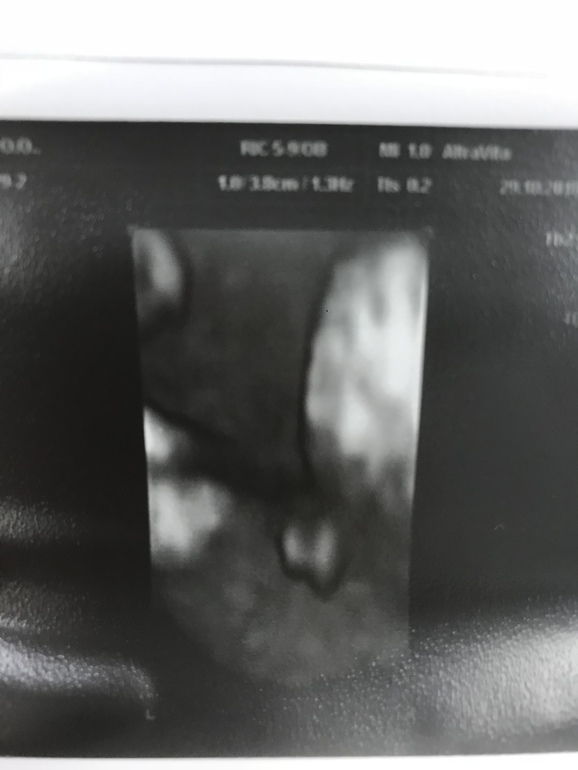

У вас на 2 фотке-писюн уже торчал?

А то я думаю, кто у меня - не пойму, губы или яички...

врач говорит девочка, а я после 3 парней не верю 😂🙈

У нас мальчик, на 12ти неделях было вот так